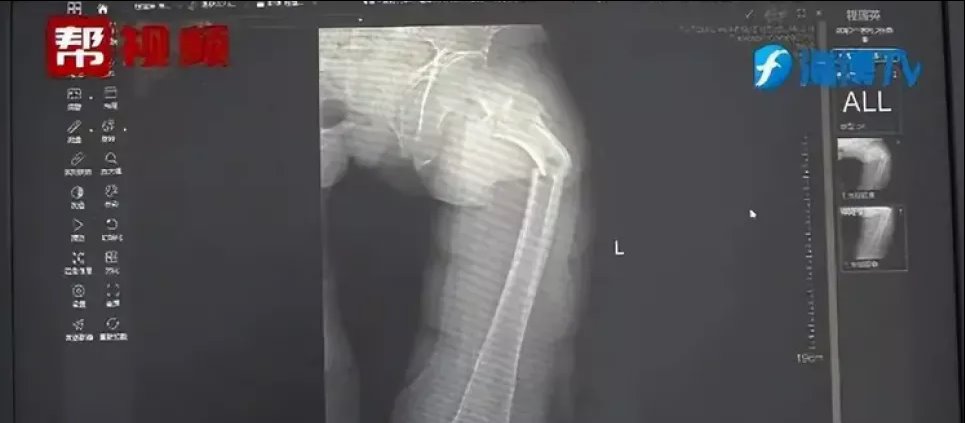

Рентгеновский снимок. Фото: Oddity CentralБедренная кость считается твердой или второй по твердости костью в человеческом теле, но 35-летний мужчина в Китае якобы умудрился сломать ее, просто кашлянув. Об этом рассказывает Oddity Central.

Рентгеновский снимок показал, что господин Е получил перелом бедренной кости, но его рассказ о кашеле не имел никакого смысла, и не было никаких признаков какой-либо физической травмы. Чжун и его команда решили провести дальнейшее исследование, расспросив пациента о его общем состоянии здоровья, пищевых привычках и образе жизни, а также провели тест на плотность костной ткани, который дал тревожные результаты. Плотность костной ткани Е походила на плотность костей 80-летнего мужчины, что было необычно даже для современных малоподвижных мужчин.